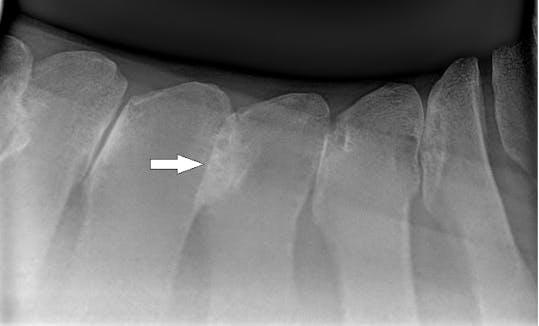

- Kissing Spine:

Overlapping Dorsal Spines: Kissing spine, also known as dorsal spinous process impingement (DSPI), is a condition that affects the spine of horses. It involves the overlapping or close contact of the dorsal spinous processes (DSP) of the vertebrae in the horse's back. These processes are bony projections along the top of the spine.